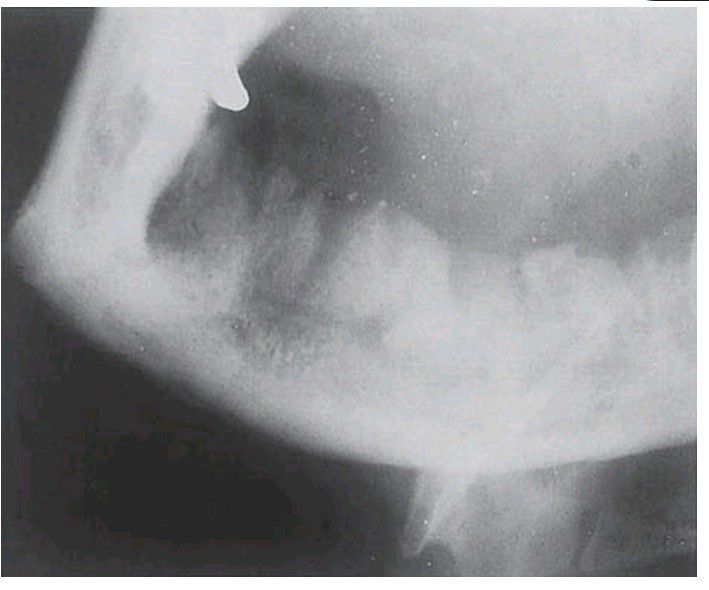

Osteomyelitis of the mandible following dental extractions. The outlines of the extraction sockets can be seen, together with dense sequestra of bone lying in a poorly circumscribed radiolucency.